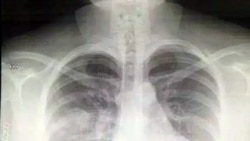

Türkmenistanyň Mary welaýatynda soňky günleriň dowamynda öýkenindäki agyry sebäpli keselhana ýüz tutýanlaryň sany artýar, administratiw merkezdäki Ýokanç keseller hassahanasy näsaglaryň akymyna döz gelip bilmän, täze syrkawlary kabul etmekden ýüz öwürýär. Bu aralykda, ilata tölegli esasda, esasan, hytaý waksinasyny sanjym etdirmek teklip edilýär, emma adamlar onuň howpsuzlygyny sorag astyna alýarlar.